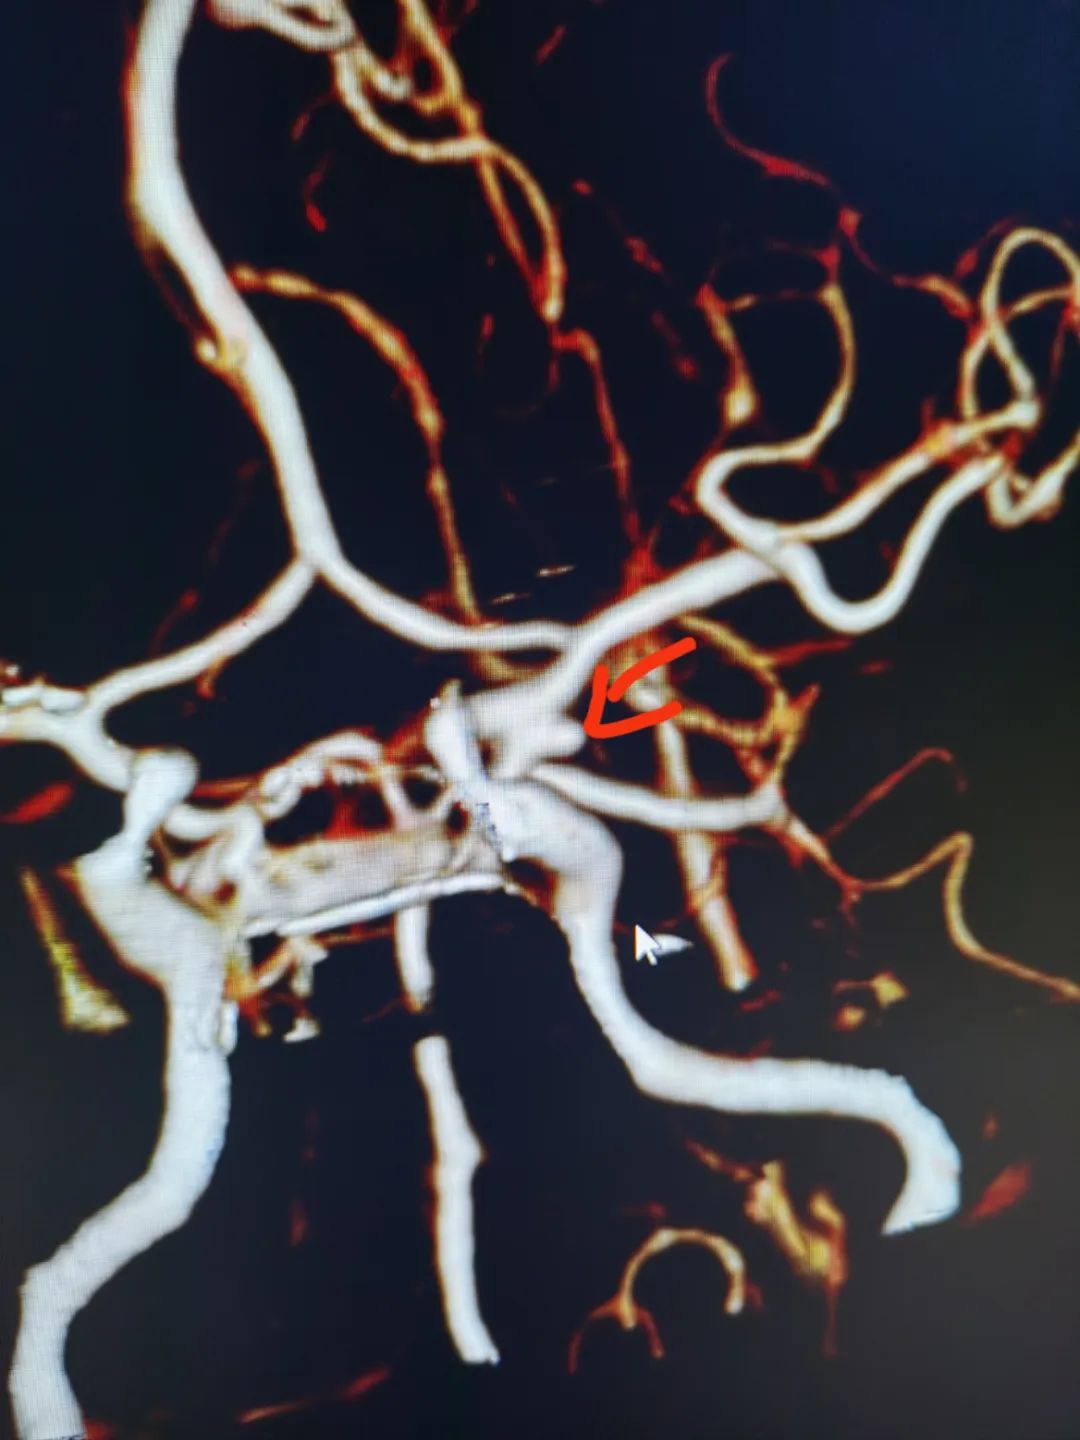

50歲的劉女士五天前深夜突發(fā)劇烈頭痛,不能忍受,伴惡心、嘔吐數(shù)次,家人急送醫(yī)院檢查。神經(jīng)外科主任施宏飛接診患者,結(jié)合患者病情、體格檢查及相關(guān)CT結(jié)果,診斷其蛛網(wǎng)膜下腔出血明確,為盡快明確患者病因,立即開(kāi)辟綠色通道行急診頭顱CTA,顯示左側(cè)后交通動(dòng)脈瘤。

施宏飛主任帶領(lǐng)神經(jīng)外科介入團(tuán)隊(duì)針對(duì)患者病情,緊急討論考慮蛛網(wǎng)膜下腔出血為動(dòng)脈瘤破裂所致出血。動(dòng)脈瘤是由于動(dòng)脈壁的病變或損傷,形成動(dòng)脈壁局限性或彌漫性擴(kuò)張或膨出的表現(xiàn)。顱內(nèi)動(dòng)脈瘤管壁比正常血管壁薄,易破裂出血,破裂后引發(fā)蛛網(wǎng)膜下腔出血,患者多表現(xiàn)為難以忍受的頭痛,是急危重癥疾病,死亡率極高。

施宏飛主任提醒:如有不明原因突發(fā)劇烈頭痛,應(yīng)盡早進(jìn)行頭部CT檢查,如發(fā)現(xiàn)蛛網(wǎng)膜下腔出血,應(yīng)進(jìn)行腦血管CTA或DSA檢查明確是否存在顱內(nèi)動(dòng)脈瘤。